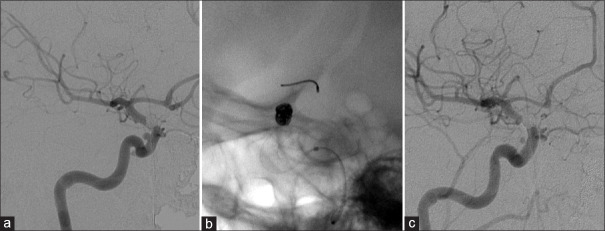

镍和钴经常出现在用于制造动脉瘤夹和血管内假体(如管道栓塞装置(PED))的金属合金中。镍过敏症可影响多达 15% 的人群,但在接受血管内支架置入术的患者中却很少出现。在此,我们介绍了一名 35 岁女性的病例,她在置入 PED 后出现过敏症状,后来通过斑贴试验证实她对镍和钴都过敏。幸运的是,她对药物治疗反应良好,因此无需手术干预。据我们所知,这是第一例关于症状性镍过敏的报告,也是第二例关于 PED 引起症状性钴过敏的报告。尽管其发病率较低,但我们认为外科医生应在术后积极询问患者有关过敏症状的情况,以便及早诊断和治疗。

Nickel and cobalt are frequently found in metallic alloys used in the manufacture of aneurysm clips and endovascular prostheses, such as the pipeline embolization device (PED). Nickel hypersensitivity can affect up to 15% of the population, however, it is very rarely overt in patients who undergo endovascular stent placement. Here, we present the case of a 35-year-old woman who developed allergic symptoms after PED placement and was later confirmed to be allergic to both nickel and cobalt by patch testing. Fortunately, she responded well to pharmacologic treatment, rendering surgical intervention unnecessary. To the best of our knowledge, this is the first report of symptomatic nickel hypersensitivity, and the second report of symptomatic cobalt allergy caused by the PED. Despite its low prevalence, we believe that surgeons should actively inquire patients in the postoperative period about allergic symptoms, to facilitate early diagnosis and treatment.